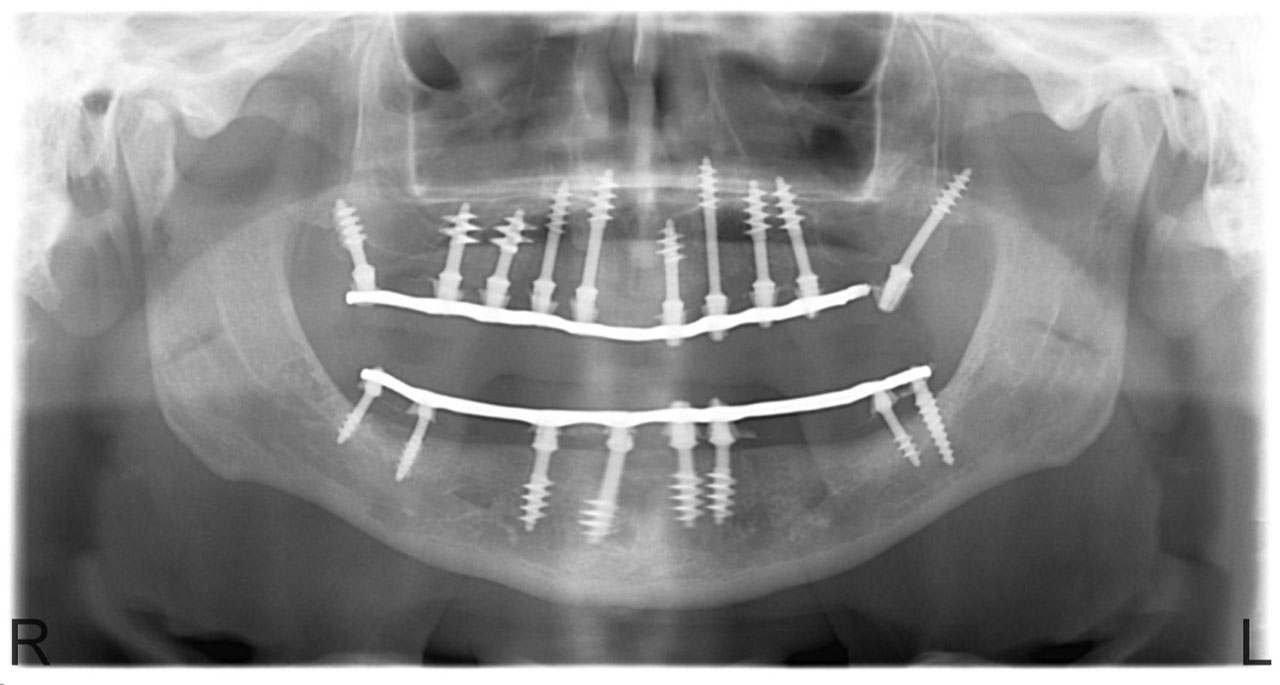

Sikerét mindenekelőtt a gyorsaságának köszönheti, hiszen a mai rohanó világban kinek van ideje, kedve fogatlanul otthon ülni heteket, hónapokat a fogpótlásra várva? Az Ihde implantációs eljárás során a páciens azonnal, de legkésőbb 72 óra múlva egy rögzített (tehát nem mozgó, nem kivehető) pótlással hagyja el a rendelőt. Ez az egyedülállóan gyors eljárás annak köszönhető, hogy azonnal tudunk implantálni szinte bárhova, akár foghúzás után is, továbbá a művelet nem jár nagy feltárásokkal, nincs szükség csontbeültetésre, így a gyógyulás folyamata is nagyon gyors és a beültetés technikájának köszönhetően maximum 72 óra múlva a korona is feltehető. Tehát ennyi idő alatt foga lesz a betegnek és az implantátum azonnal terhelhetővé is válik.

Az eljárás mellett szól az is, hogy nagyon biztonságos. A cég adatai alapján a beültetett implantátumok 98.2%-a sikeres. Az azonnali terhelésű implantátumokkal rögtön, akár foghúzás után is szinte bárhová lehet implantálni, bárkinek, legyen szó cukorbeteg, dohányos, vagy akár csontritkulásban szenvedő páciensről. Ennek köszönhető, hogy a betegek 99%-ánál alkalmazható a módszer.

Természetesen, az Ihde Azonnal Terhelhető Implantátum Rendszer alkalmazása speciális szaktudást igényel, így elengedhetetlen az orvosok gondos és folyamatos képzése. Ez, illetve a kiváló minőségű svájci alapanyagok és a sok évtizedes, precíz, innovatív gyártási technológia együttese adja, hogy a cég kiemelkedően magas (98,2%-os) sikert ér el, az Ihde implantátumok bent maradásának mérésekor.